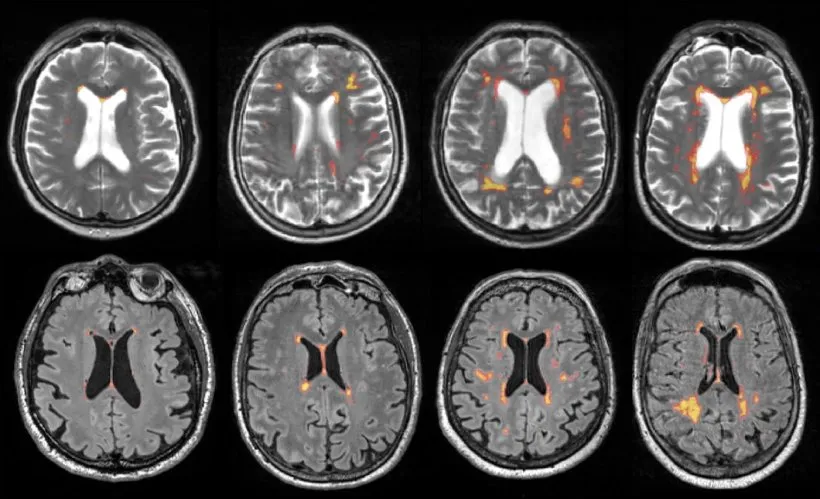

Um die Ursache der kognitiven Beeinträchtigungen eindeutig vaskulären Veränderungen zuzuordnen, sind bildgebende Verfahren des Gehirns unerlässlich. Die Magnetresonanztomographie (MRT) gilt hierbei als der Goldstandard. Sie ermöglicht uns eine hochauflösende Darstellung der Gehirnstruktur und macht kleinste vaskuläre Schäden sichtbar, die mit anderen Methoden oft nicht erkennbar wären. Wir können damit nicht nur größere Schlaganfälle, sondern auch sogenannte stumme Infarkte (Lakunen) und Veränderungen in der weißen Substanz, die als Leukaraiose bezeichnet werden, präzise lokalisieren und quantifizieren. Insbesondere spezielle MRT-Sequenzen wie die FLAIR-Aufnahme (Fluid-Attenuated Inversion Recovery) sind äußerst sensitiv für diese subtilen Läsionen, die auf eine chronische Minderdurchblutung des Gehirns hinweisen.

Was sind "stumme Infarkte" und "Leukaraiose" auf den Bildern?

Die Begriffe "stumme Infarkte" und "Leukaraiose" beschreiben typische Veränderungen im Gehirn, die durch vaskuläre Erkrankungen verursacht werden. Stumme Infarkte, oft auch als Lakunen bezeichnet, sind kleine, scharf begrenzte Infarkte, die durch den Verschluss kleiner Hirnarterien entstehen. Sie verursachen oft keine offensichtlichen neurologischen Symptome, können aber in ihrer Summe zu erheblichen kognitiven Defiziten führen. Die Leukaraiose bezeichnet Veränderungen in der weißen Substanz des Gehirns, die auf eine chronische Unterversorgung mit Blut und Sauerstoff zurückzuführen sind. Auf MRT-Bildern erscheinen diese Bereiche als unscharf begrenzte, helle Flecken. Beide Befunde sind wichtige Indikatoren für eine zerebrovaskuläre Erkrankung und spielen eine Schlüsselrolle bei der Diagnose der vaskulären Demenz.